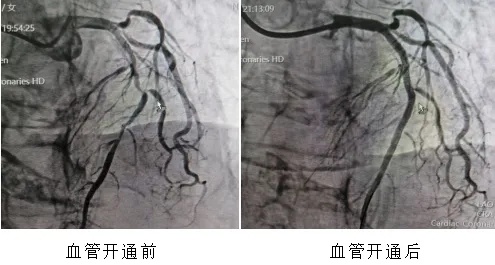

19:50第2台:血管开通时间70分钟

22分钟、70分钟、36分钟、18分钟、12分钟——这是5颗心脏血管从“断流”到“复流”,解除堵塞病变的时间。如此高密度、高效率的连续急救,绝非偶然,它是我院胸痛中心标准化、流程化救治能力的集中体现。它的背后,是院前院内无缝联动,120急救车上已完成的心电图传输与初步诊断,患者“未到,信息已到”,导管室提前启动;是术前早已启动的医院胸痛中心绿色通道——患者到我院后可绕行ccu和(或)急诊科,直接进入导管室,最大限度压缩术前准备时间;更是心内科、急诊科、心电图室、导管室护理团队等多学科团队的无缝咬合,高效协作。这是急诊急救体系建设的力量。